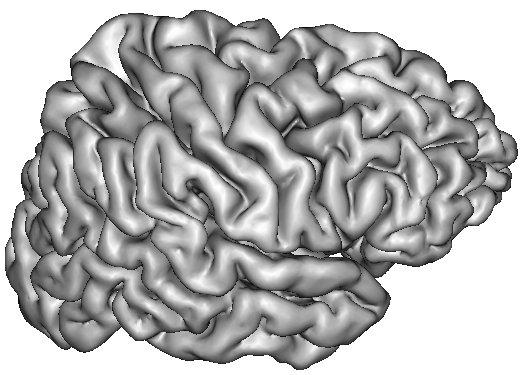

The resulting grey/white interface can be converted into a mesh endowed with the spherical topology, which will be inflated by some other Brainvisa treatments for visualization purpose (Ana Inflate Cortical Surface):

A dilation of this interface towards the outer brain edges may lead to nice 3D rendering of the cortical surface, which are easy to read because the folds are opened (Ana Get Opened Hemi Surface) :